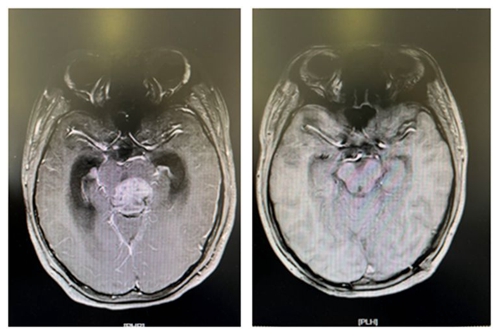

术前肿块影像                                                术后全切影像